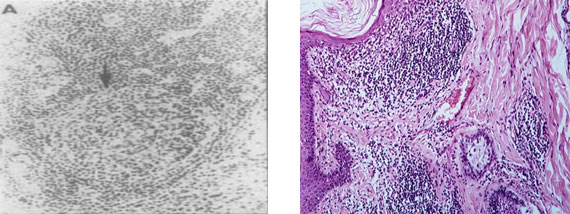

На рис. 6 представлены фото фолликулоподобных структур в синовиальной оболочке при РА. Видно, что эктопические герминативные центры находятся на разных стадиях своего формирования и функционального состояния. Наличие очагов эктопического лимфоидного неогенеза с герминативными центрами позволяют выделить определённые патофизиологические варианты РА [31].

Рис. 6. Видны множественные эктопические герминативные центры (фолликулоподобные структуры) в синовиальной оболочке при РА на разных стадиях своего развития (Х 100), по материалам [78]

Как указывалось выше, принципиально единообразные патоморфологические изменения при системной прогрессирующей дезорганизации рыхлой волокнистой соединительной ткани свойственны всем нозологическим формам ИВРС. Это же касается и лимфоидного неогенеза. В качестве иллюстрации сказанного приводим рис. 7, где представлены фолликулоподобная структура в синовиальной оболочке при РА слева и фолликулоподобная структура в дерме и в мышечной ткани при СКВ. Видно, что морфологическая организация этих структур при РА и СКВ имеет черты определённого сходства. Важен тот факт, что процент мононуклеаров и нейтрофилов, подвергшихся апоптозу и находящихся в фолликулоподобных структурах при СКВ статистически значимо превышал аналогичные показатели в контрольной группе и коррелировал со степенью тяжести клинического течения СКВ [24].

Рис. 7. Слева фолликулоподобная структура с центром размножения (стрелка) в синовиальной оболочке при РА (Х 50), по материалам [173]. Справа фолликулоподобные структуры в дерме и в мышечной ткани при системной красной волчанке, Х100, по материалам [24]